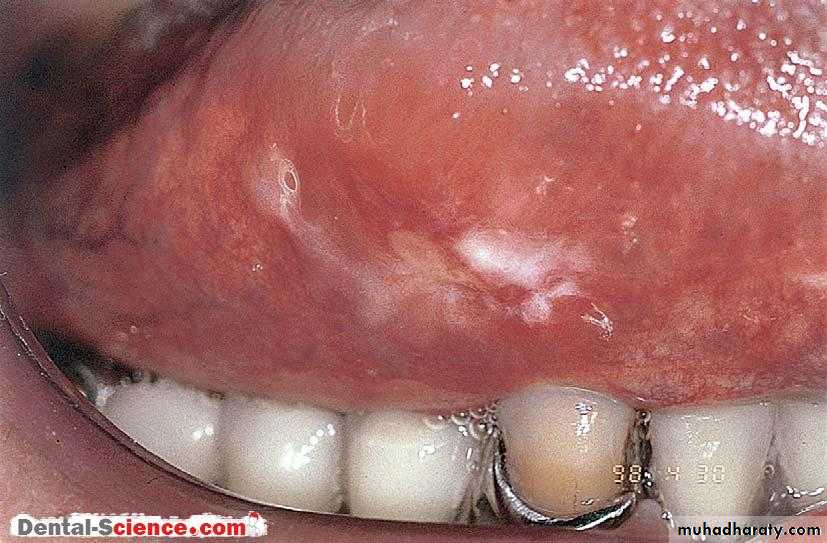

The oral mucosa is affected in a significant proportion of cases and the disease usually presents as coalescent white lesions on the buccal mucosae or palate